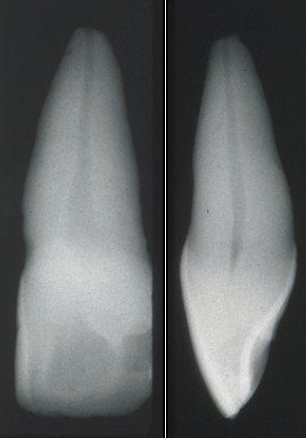

What is the root shape of central incisors?

Usually straight

What is the root shape of lateral incisors?

Usually apical curvature to distal or palatal

What is the root shape of canines?

Long root, usually apical curvature

What is the canal shape of a maxillary central incisor?

Usually round

What is the canal shape of a maxillary lateral incisor?

Usually oval / round